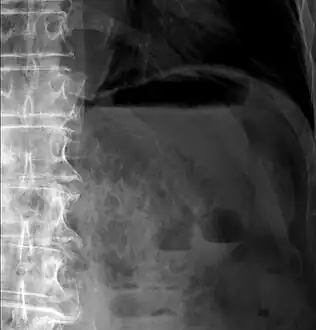

Pneumatosis intestinalis

Pneumatosis intestinalis (also called intestinal pneumatosis, pneumatosis cystoides intestinalis, pneumatosis coli, or intramural bowel gas) is pneumatosis of an intestine, that is, gas cysts in the bowel wall.[1][2] As a radiological sign it is highly suggestive for necrotizing enterocolitis. This is in contrast to gas in the intestinal lumen (which is relieved by flatulence). In newborns, pneumatosis intestinalis is considered diagnostic for necrotizing enterocolitis, and the gas is produced by bacteria in the bowel wall.[3] The pathogenesis of pneumatosis intestinalis is poorly understood and is likely multifactorial. PI itself is not a disease, but rather a clinical sign. In some cases, PI is an incidental finding, whereas in others, it portends a life-threatening intra-abdominal condition.